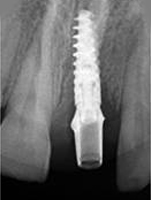

Single Tooth Implant

X-ray of Implant

X-ray of Implant + Abutment